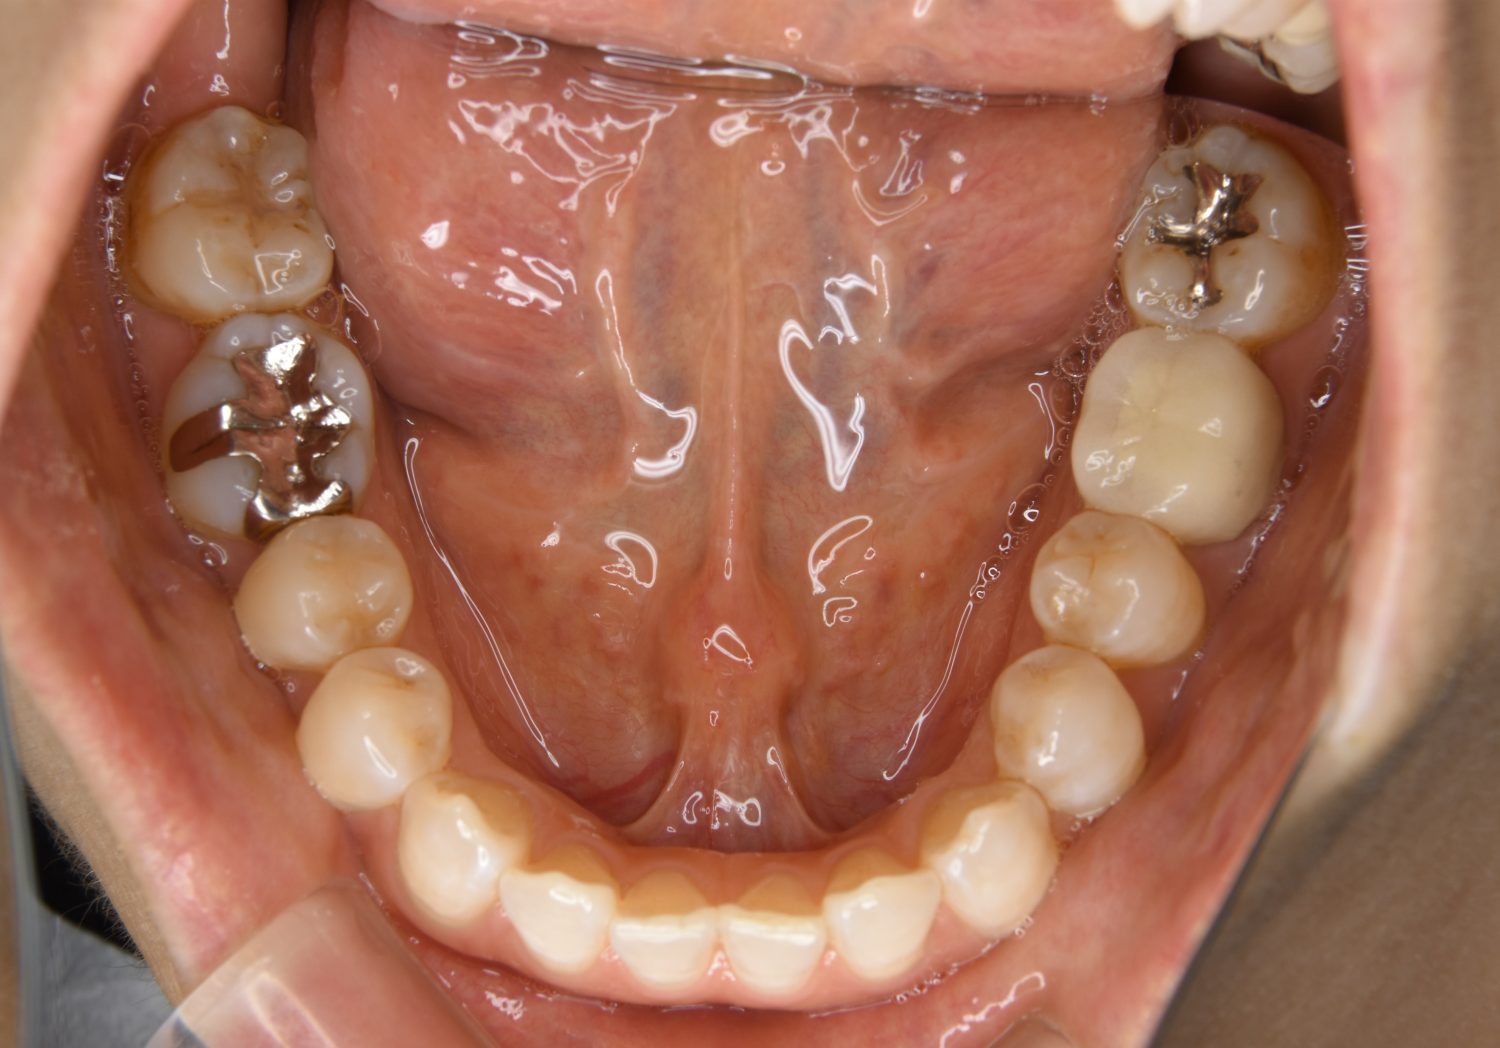

叢生の症例紹介①

Before

After

主訴

前歯のガタガタが気になる。

治療内容

上顎左側第一小臼歯を抜歯し、アライナー(インビザライン)にて治療を行いました。

治療費

1,150,000 円(税込)

治療期間

23ヶ月

通院回数

13回

想定されたリスク

※歯根吸収、歯肉退縮、歯髄壊死、顎関節症状

※アライナー(インビザライン)は日本の薬機法未承認の矯正装置であり、医薬品副作用被害救済制度の対象外となる場合があります。

左上の側切歯が完全に内側に入り込んでいる状態でした。左上の第一小臼歯のみ抜歯を行い治療を行うことで機能面および審美面を改善しました。